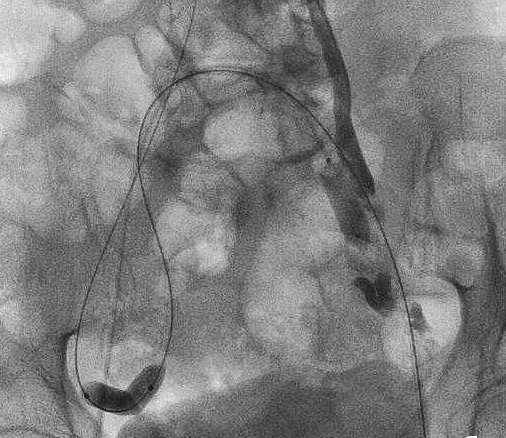

三、经股静脉导管术 卵巢静脉选择性造影常经股静脉或者颈内静脉两种途径。股静脉途径往往更常用,主要是由于造影室的设计包括射线增强器放置与病人和监视器放置的相对位置所决定。 1. 左侧卵巢静脉导管术 先放置5-7F的股静脉套管,然后用一根7F的Judkins 钩形状的引导导管(心脏血管内介入)选择左肾静脉。这跟引导导管在前行进入左肾静脉的过程中,可以选择左卵巢静脉的开口。一旦固定好后,在导丝引导下置入一根5 F(1.67mm)外层附有亲水物质的同轴导管,至大约平骶髂关节水平,并且进入盆腔卵巢静脉丛。

2. 右侧卵巢静脉导管术 从下腔静脉找右卵巢静脉,需要选择性置入一个角度更大的钩形引导导管。这种SimmonⅠ型和Ⅱ型导管。仍然用一根5F(1.67mm)外层附有亲水物质的同心导管在上述引导导管中前进。为了能让5 F(1.67mm)的SimmonⅠ型或Ⅱ型导管选择到右卵巢静脉,一般用一根极细的导丝引导一根同心微导管进入右盆腔。进行右侧卵巢静脉造影,然后注射与上述相同的明胶海绵/鱼肝油酸钠混合物,再用栓塞弹簧圈将右卵巢静脉主干闭塞。